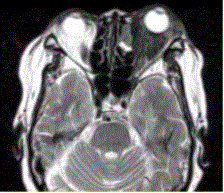

问题 患者女,64岁,左眼突出5年余。查体左眼球前突6mm,眼球运动自如,眼底无异常,下睑扪及边界不清、质软的肿块,视力正常,MR表现如下图。 经抗生素及激素治疗后好转,则诊断支持

选项 A.炎性假瘤 B.眼型Grave病 C.黑色素瘤 D.转移瘤 E.眼眶海绵状血管瘤 F.弥漫型淋巴管瘤

答案 A

解析 A